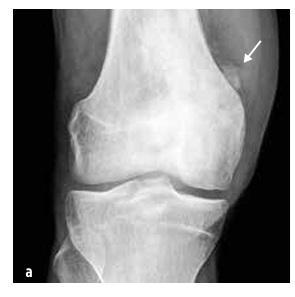

Slika 5

Osteosarkom distalnega dela stegnenice